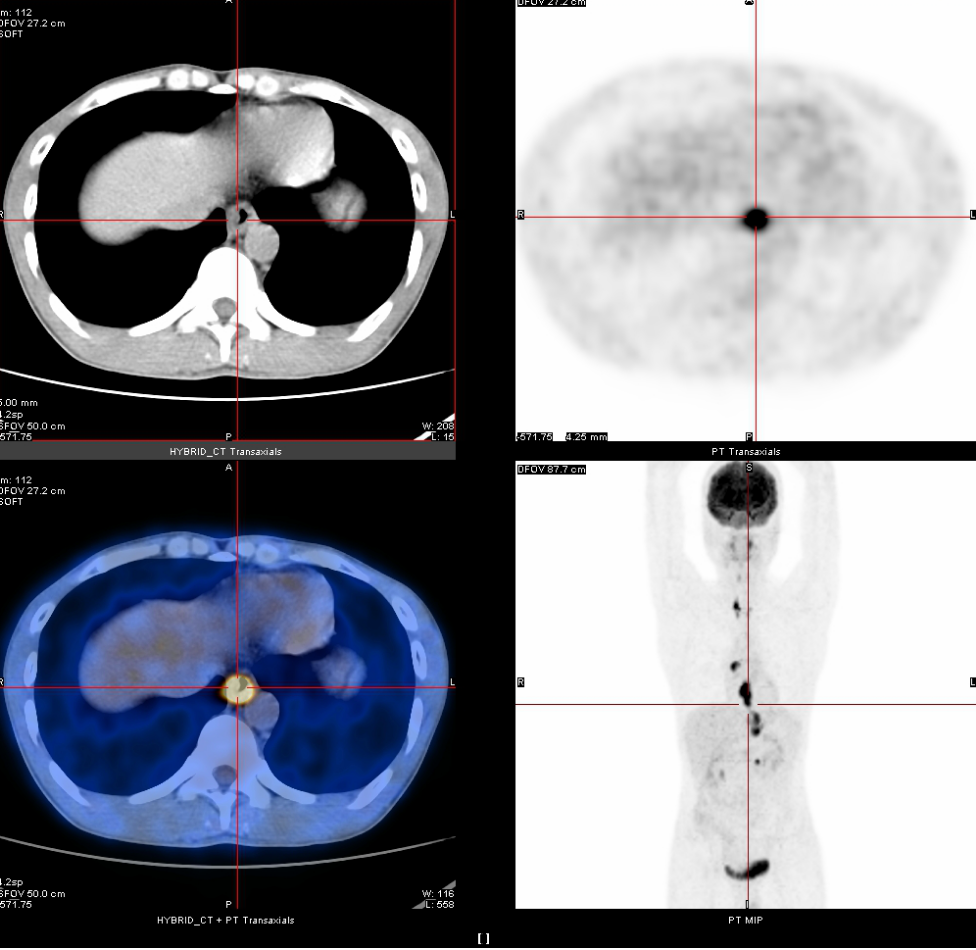

2020年3月13日

全身PET-CT示:1、食管胸中下段管壁不规则增厚,代谢增高,考虑食管癌。2、上纵隔胸廓入口区气管两旁、右下肺静脉后方、贲门区、肝胃间隙、降主动脉后方、膈肌脚后方、腹膜后腹主动脉左旁(左肾门下方平面)见多发高代谢肿大淋巴结,考虑淋巴结转移,建议随访复查。3、右肺上叶前段胸膜下小结节影,代谢未见增高,建议随访复查。4、右肺下叶外基底段条索影,考虑慢性炎性改变。5、双侧上颌窦轻度慢性炎症。6、双侧颈部多发小结节影,代谢未见增高,考虑淋巴结慢性炎性增生。7、肝左叶内侧段小钙化灶。